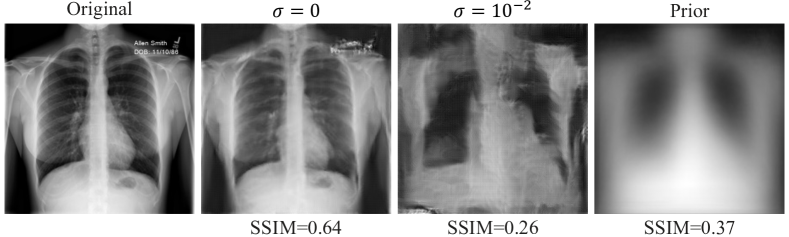

A straightforward approach to avoid data recovery by a server-side gradient inversion attack is the addition of random noise to the model updates before they are sent to the server [31]. Here, we explore a simple DP protocol that adds calibrated Gaussian noise, with zero mean, based on the gradient magnitudes of the model updates (see Section II-C) and compare it to when all clients use DP-SGD as their local training optimizer. As an illustrative example, we first evaluate the simple DP protocol on client 9, which is the high-risk client, using model updates that are sent at round 90. As shown in Fig. 6(c), the image reconstruction quality, as measured by the SSIM between original and recovered images, expectedly degrades as more noise is added to model updates from the client.

The SSIM value between the prior which is used to initialize the gradient inversion attack (see II-B) and the original image is 0.37 (see Fig. 7). This can be considered as a lower bound of this metric during the attack. In addition, as the noise level increases, reconstructions from model updates with added DP become closer to the prior image and less similar to the original training image. This indicates that a privacy setting () allowing only a reconstruction with a SSIM value equal to or less than that between the original image and the prior could be considered “safe”. For instance, as shown in Fig. 7, this behavior can be observed for the high-risk client 9 at FL round 90 and noise added with .